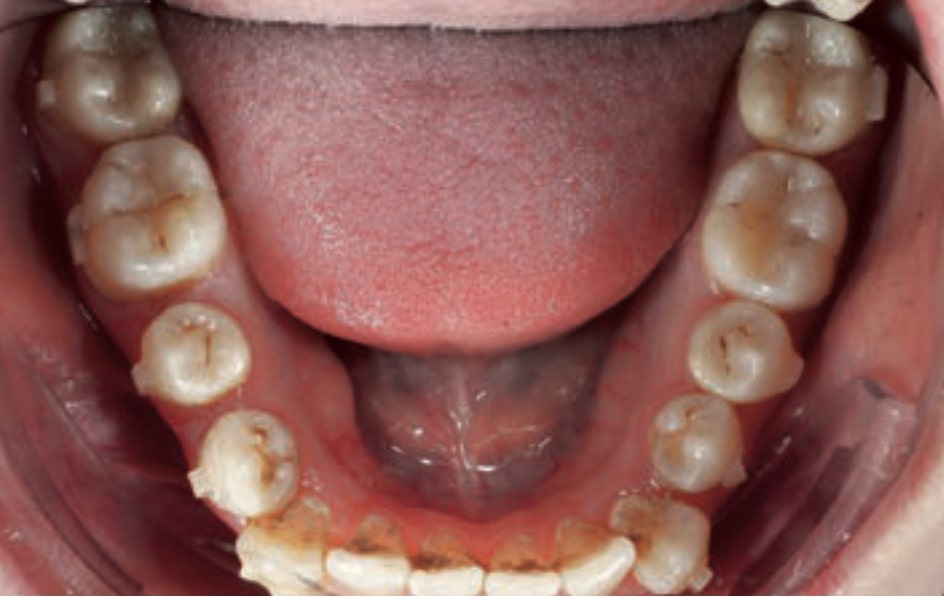

Chief complaint: The patient, a 19-year-old woman, was evaluated to undergo orthodontic treatment using the Angel Aligner Pro system. She presents with a skeletal Class III, mesofacial, with a dental Class III malocclusion and a 2 mm deviation of the lower midline to the left. Teeth 33 and 43 are out of the arch and cortical bone, with a crossbite issue on tooth 33. Fortunately, no functional issues affecting swallowing or breathing have been detected. The patient’s motivation for starting treatment was a general review of her dental and aesthetic health. The soft tissue analysis reveals mandibular protrusion that influences her facial profile. This diagnosis highlights the need for a comprehensive approach to address dental and skeletal misalignments, improving both the patient’s functionality and facial aesthetics.

- Dental Class III, 2 mm deviation of the lower midline to the left. 33 and 43 out of the arch and the cortical bone.

- Crossbite of 33.

- Distalize third and fourth quadrant